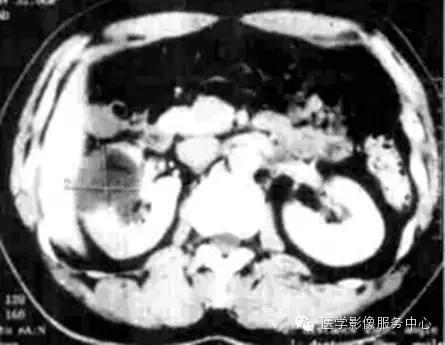

影像学检查是诊断肾淋巴管瘤的重要手段 。CT和MRI检查可以显示肿瘤的大小、位置和形态特征。然而,仅凭影像学表现难以与其它肾脏肿瘤鉴别。最终确诊往往需要依靠病理学检查。